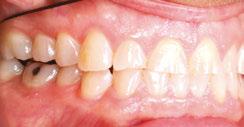

Figures 6 through 9 demonstrate a patient successfully treated with NiTime Aligners following the patient’s rejection of other systems. Figures 6 and 8 display pre- and posttreatment photos of a patient that presented with a Class II malocclusion and normal OB/OJ. This patient has teeth Nos. 7 and 10 missing congenitally. Note that the patient was treated as a child and has a canine substitution due to the missing lateral incisors. Recession was noted on tooth Nos. 2,3, 4, 5, 9, 11, 13, 14, 22, 24, 26, and 27. The patient tried labial and lingual brackets unsuccessfully, as well as a leading clear aligner to correct her malocclusion as an adult. In all three treatments, the patient could not tolerate the mechanics due to increased discomfort and was unable to complete therapy.

It is important to note that there was no refinement required for this case, and the patient finished in 26 weeks with 26 trays. Although the patient presented with significant recession, it did not worsen with treatment. As demonstrated in Figure 9, teeth aligned as planned by the OrthoFX treatment plan shown in Figure 7. Overlays of the actual results with the original treatment plan indicate a high level of predictive accuracy. Not only was a satisfactory result produced from the patient wearing the aligners, but the accuracy is quite high for the NiTime material despite the patient wearing it significantly less than the traditional 22 hours per day.

Figure 8: Class II malocclusion posttreatment. Left column pretreatment. Right column posttreatment 22 stages